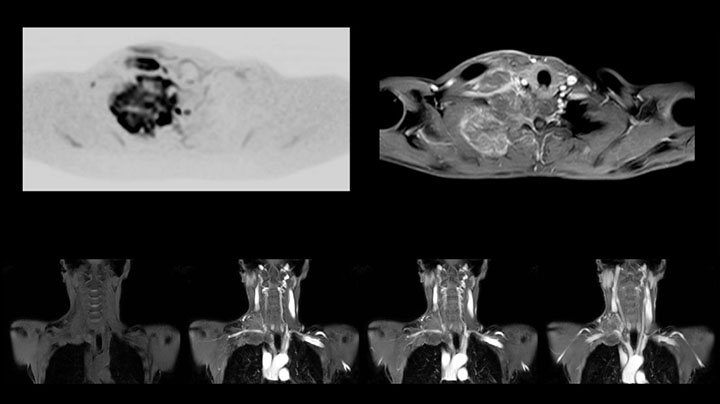

A 61-year-old female with a malignant lymphoma underwent an MRI exam with whole body diffusion weighted imaging (DWIBS) as well as PET. On the images shown, the resolution of DWIBS is better than PET, which allows visualization of the small pelvic lesions and almost no distortion is seen in the neck area.